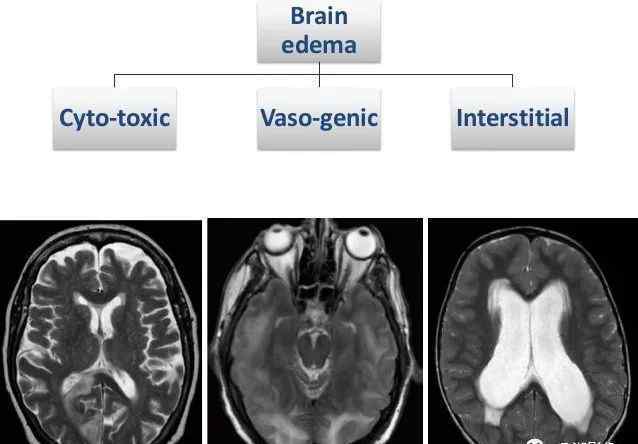

脑水肿

脑部疾病是临床MRI检查的重中之重,脑水肿是脑部疾病最常见的基本病理改变之一,在很多脑组织疾病中都可以见到。因此,了解脑水肿的磁共振表现对脑部疾病的磁共振诊断非常重要。

在病理学上,脑水肿可分为三种类型,即:

血管生成性水肿

细胞毒性水肿

间质性水肿